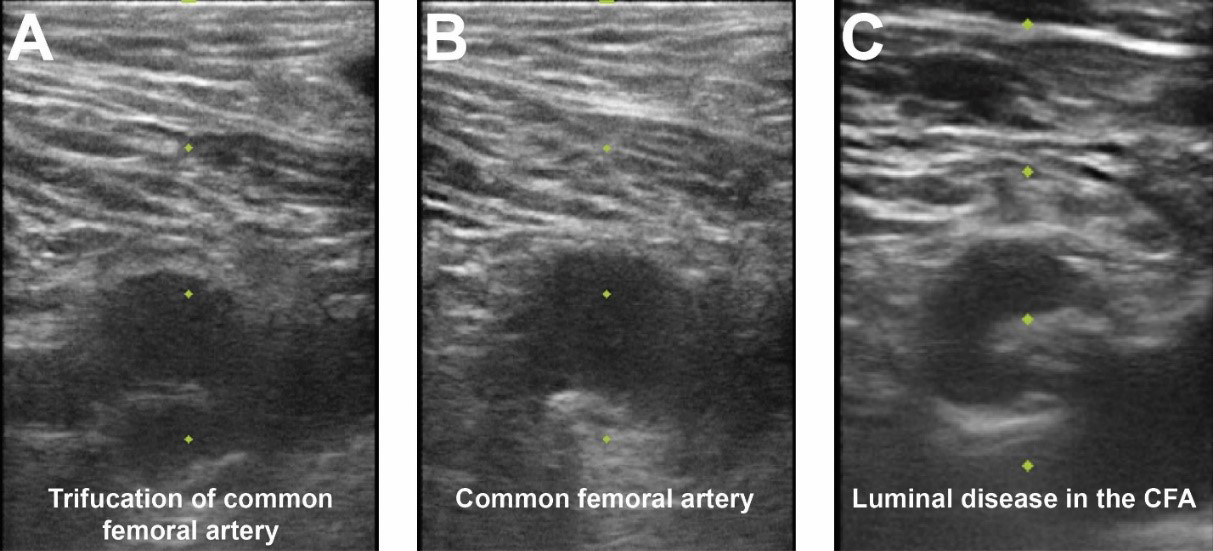

Fig. 3.Femoral access ultrasound. (A) Femoral artery ultrasound shows a trifurcation of the CFA and femoral vein to image right. (B) Superior to the CFA bifurcation is seen in an area amenable for vascular access. (C) CFA ultrasound noting significant luminal atherescolosis.